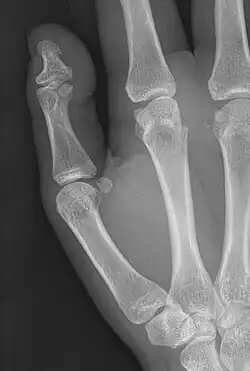

| Brachyphalangy of the thumb's distal phalanx, also known as brachydactyly type D, with otherwise normal phalanges of the 2nd-5th digits | |

| Symptoms | Having a phalange(s) shorter than average |

Brachyphalangy is a condition in which one or more of the phalanges of the fingers and toes are smaller than normal.[1]

This condition is caused by either fusion or early closure of the phalange's growth plate. One example is brachydactyly type D, which is caused by an early closure of the thumb's distal phalange, leading to a congenitally short thumb with a similarly short and wide thumb nail.